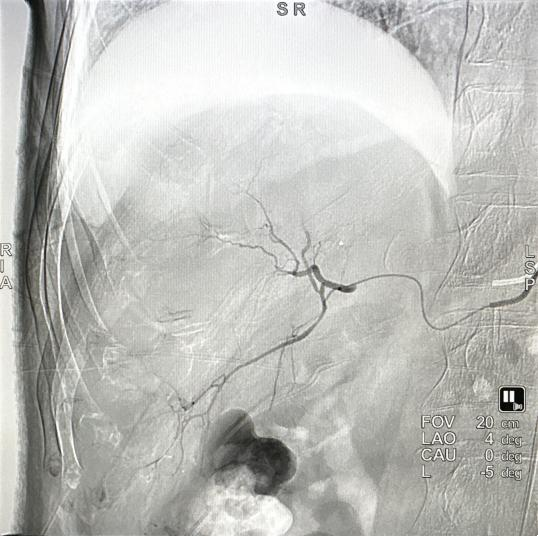

一切准备就绪,放射科主任罗谞成协助朱晖教授进行介入手术。穿刺点局麻后,朱晖教授在B超引导下穿刺插管,在DSA设备的帮助下,对肝右及肝中动脉较纤细、远段分支位置的六处结节进行精准打击。术中,朱晖教授把导管送进肝肿瘤的供血动脉中对其进行栓塞,阻断其血供,使肿瘤趋于坏死,并向病灶集中释放药物。手术非常顺利,历时仅2小时。由于患者血小板较低,为防止血肿的发生,朱晖教授亲自按压止血30分钟,确定穿刺处无出血、无血肿后,再进行加压包扎。最后安全护送患者至病房,并进行了详细的术后指导。患者及家属不胜感激:“这趟求医之路实在值得,朱教授又救了我一命,谢谢你们!”短短三次“相遇”,用心用情的“守护”,铸就一段医患深情。

术后造影